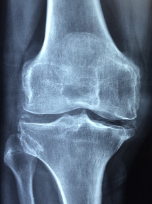

무릎 관절염 증상

무릎 골관절염의 증상은 다음과 같습니다.

- 통증 : 무릎 관절염의 가장 흔한 증상은 무릎 주위의 통증입니다. 이는 특히 오래 앉아 있거나 서 있거나 움직이는 경우에 적용됩니다.

- 뻣뻣함: 무릎의 골관절염은 무릎 관절의 뻣뻣함을 유발합니다. 무릎 관절의 움직임이 제한되어 일어나거나 앉기가 어려울 수 있습니다.

- 붓기: 무릎의 골관절염은 무릎 주위에 붓기를 유발할 수 있습니다. 붓기는 무릎 관절에 더 많은 압력을 가하고 더 많은 통증을 유발합니다.

- 플러싱: 무릎 관절염은 관절 주변 조직의 염증으로 인해 무릎 주변에 열감을 유발할 수 있습니다.

- 소음: 무릎의 골관절염은 무릎 관절의 윤활제 분비 감소로 인해 뼈 마찰로 인한 부적절한 소음을 유발할 수 있습니다.

무릎 골관절염의 증상은 진행 정도에 따라 다릅니다. 처음에는 경미한 통증이 있을 수 있으나 무릎 관절이 진행됨에 따라 무릎 관절의 기능이 저하되어 통증이 심해질 수 있습니다. 무릎 골관절염이 의심되는 경우에는 증상이 악화되기 전에 적극적인 치료와 예방적 조치를 취하여 증상이 악화되지 않도록 해야 합니다.